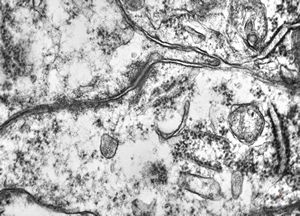

![F,23y. | n.suralis - hypertrophic demyelinating neuropathy [onion bulb] F,23y. | n.suralis - hypertrophic demyelinating neuropathy [onion bulb]](../img/OGDEM/015 Soft tissues/0077.jpg)

F,23y. | n.suralis - hypertrophic demyelinating neuropathy [onion bulb]